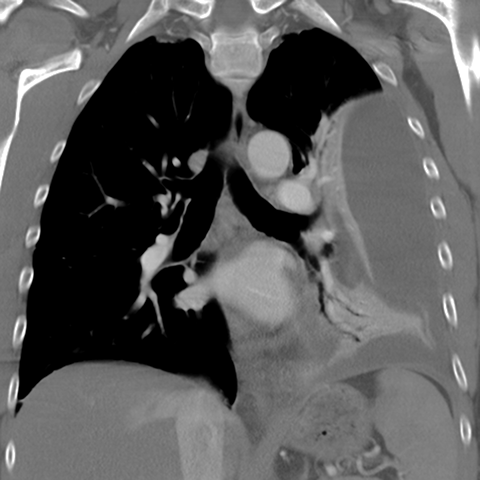

Large, Loculated Pleural Effusion [3 of 3]